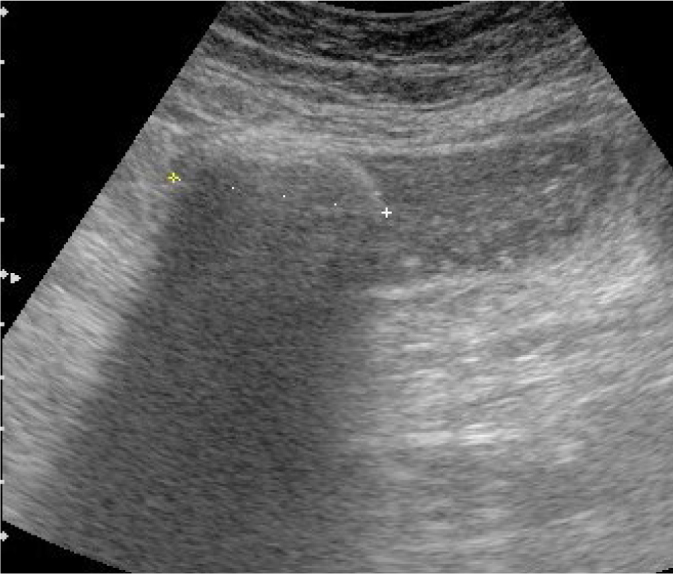

The aim of this paper is to present our experience in transabdominal ultrasonography of ileocecal valve lesions. The ileocecal valve, located in the central part of the ileocecal bowel segment, is rarely the primary site of disease processes. It is usually involved by pathologies in adjacent bowel segments. These are primarily infectious diseases such as yersiniosis, campylobacteriosis and salmonellosis. Typical location of Crohn's lesions also promotes valve involvement. The appearance of the lesions in these cases is characterized by a symmetrical submucosal thickening of the bowel involved over a longer segment. Non-malignant valvular hyperplasia is relatively commonly identified as lipomatosis, manifested by symmetrical enlargement and smooth outlines. However, valvular lipoma causing an asymmetrical hyperechoic bulge is a rare finding. ileocecal valve lipomatosis or lipoma should not be misdiagnosed as a lipoma of the cecoascending part of the colon and, the other way round, a right colonic lipoma should not be mistaken for a fatty valve. Polyps on the ileocecal valve, although sometimes detected, were not identified in our material. Adenocarcinoma, which is found in the cecum in approximately ¼ of cases, is the most common malignancy, followed by neuroendocrine tumor and, rarely, lymphoma. In three cases of malignant involvement of the ileocecal valve, we observed irregular hypoechoic thickening with complete loss of wall stratification, with the lesions causing symptoms of small bowel obstruction in two of these cases. The nearly forgotten ileocecal valve syndrome, also known as Bauhin's ileocecal valve syndrome, characterized by intermittent right iliac fossa pain, is also briefly discussed. Transabdominal ultrasound can be used as an initial diagnostic tool in some of these pathologies.

Abstract Image